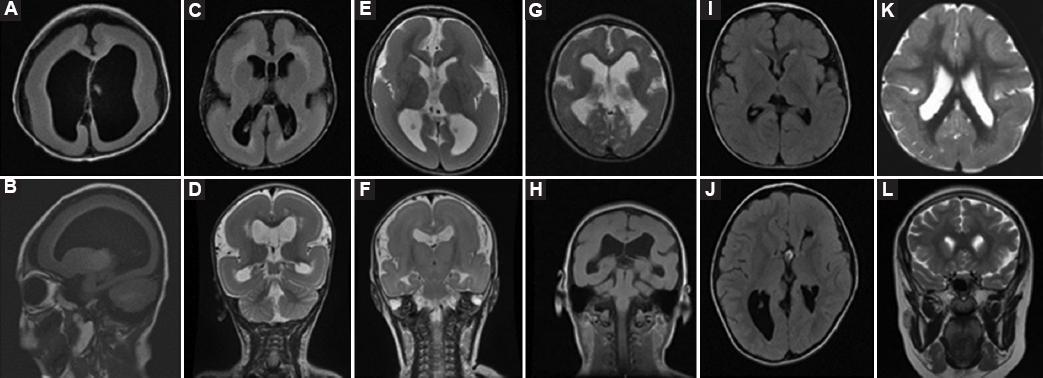

According to the classification system for LIS modified by Dobyns15, in brain MRI, the most frequent was Grade 4 correspond to pachygyria in 9 (41%) children. We founded predominance of anteroposterior gradient (more severe lesion anterior). Furthermore, we found 4 (18%) children in Grade 2, agyria with undulation of brain cortex; 3 (14%) children in Grade 1, diffuse agyria; 3 (14%) children in Grade 3, mixed agyria and pachygyria; 2 (9%) children in Grade 5, pachygyria and SBH; and only 1 (4.5%) child in Grade 6, SBH. The two patients who died had diffuse agyria this is the most severe form. Other findings in brain MRI were agenesis of the corpus callosum, polymicrogyria, and cisterna magna (Figs. 1 and 2).

Figure 1 Classification of the brain MRI findings of children with lissencephaly according to grading system for classic lissencephaly and SBH. SBH: subcortical band heterotopia.

Figure 2 Brain MRI findings. A and B: agyria diffuse. C-F: agyria diffuse with few superficial undulations on frontal and temporal poles. G-H: agyria and pachygyria mixed, with frontal pachygyria and parieto-occipital agyria. I-J: partial pachygyria more severe anterior. K: more severe partial pachygyria posterior. L: heterotopia in subcortical band.